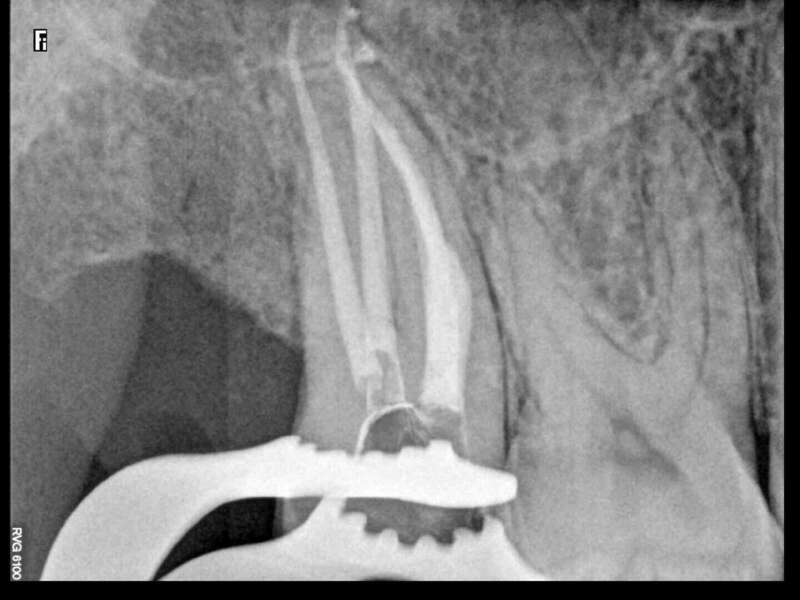

Après